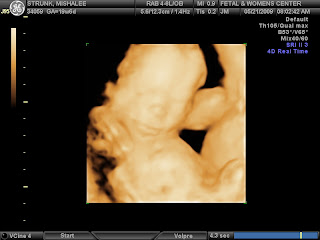

Absolutely no doubt that HE is all boy. We can't show you the proof, it's too graphic! Axel James Strunk's 20 week ultrasound looks a heck of a lot like his big brothers... he's long, string bean-ish, big feet and measuring bigger than his 20 weeks. They estimate him at 14 oz. with a due date of Sept. 30, BUT we've heard this before with Spanky and will stick with our EDD of 10-09-09

Here he is in all his glory:

Sweet little face: